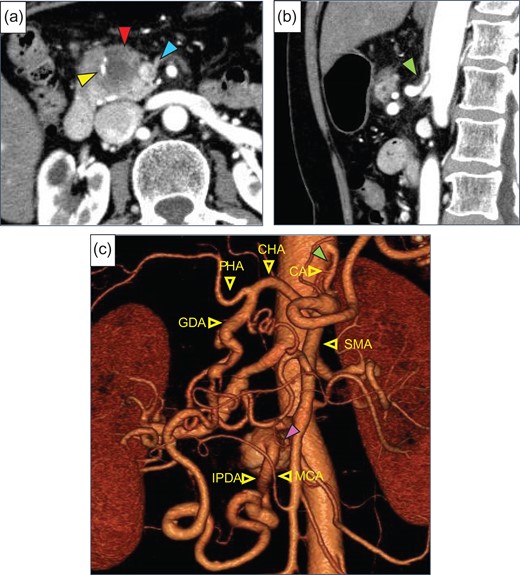

A 71-year-old woman was admitted because pancreatic head cancer was suspected on a medical checkup. Enhanced abdominal computed tomography (CT) revealed a low-density tumor, 30 mm in diameter, in the pancreatic head, and involvement of the superior mesenteric vein (SMV) with the tumor was noted (Fig. 1a). The distal side of the GDA was involved by this tumor, however, the proximal side of the GDA was not involved. CA stenosis was revealed (Fig. 1b). In addition, the developed arcade of the peri-pancreatic arteries and an aneurysm of the inferior pancreaticoduodenal artery (IPDA), 20 mm in diameter, were found (Fig. 1c). We preoperatively diagnosed the patient with pancreatic head cancer with CA stenosis due to MAL compression and aneurysm of IPDA, T3N0M0 Stage IIA (UICC seventh). We planned PD and SMV resection and reconstruction with opening of the MAL. If the hepatic arterial flow was found to be inadequate after division of the MAL, arterial reconstruction by end-to-end anastomosis of the GDA and MCA was planned.

(a) Enhanced abdominal CT showed a low-density tumor (red arrow), 30 mm in diameter, in the pancreatic head. The superior mesenteric vein (SMV, blue arrow) and gastroduodenal artery (GDA, yellow arrow) were involved by this tumor. (b) Stenosis of the celiac artery (CA) was shown (green arrow). (c) Preoperative 3D CT angiogram showed the development of pancreatic artery arcade and a saccular aneurysm (purple arrow) of the inferior pancreaticoduodenal artery (IPDA), 20 mm in diameter. CHA, common hepatic artery; PHA, proper hepatic artery; SMA, superior mesenteric artery; MCA, middle colic artery.